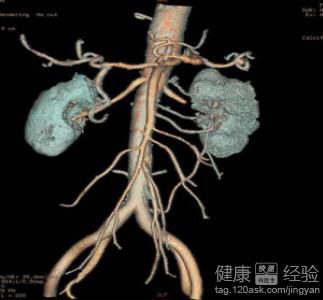

動脈栓塞指的是血塊或者進入血管內的異物稱為栓子,並且隨著血流停頓在口徑相似較小的周圍動脈或者內髒動脈的動脈內,從而造成血流障礙。動脈栓塞主要有血栓造成,而腫瘤、空氣、脂肪等也是可以成為栓子的。其中以血栓較為常見,經常發生在心血管病人。動脈栓塞,通常情況下是由栓塞、血管收縮、血管痙攣和動脈瘤引起。下面給大家具體介紹動脈栓塞的發病原因以及治療方式等。

3動脈栓塞的治療方式。非手術治療,為降低血脂和血壓,接觸血液高凝狀態,從而使側支循環形成;方法有嚴格禁煙和適當運動等藥物有阿司匹林、雙嘧達膜等;手術治療有經皮腔內血管成形術,內膜剝脫術,旁路轉流術等。